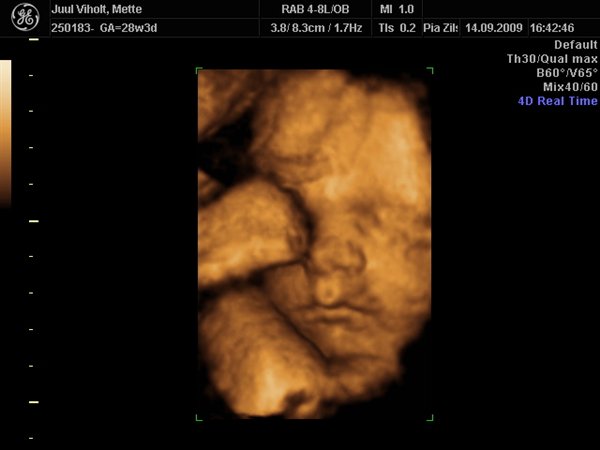

Hun ser dejlig ud, Tutski

Vi gav 1800 kr. for en scanningspakke med en kønsscanning i 17-18 uge og en 3D mellem uge 28-32.

Til 3D scanningen fik i 70 billeder printet OG på Cd, og hele scanningen med lyd på DVD.